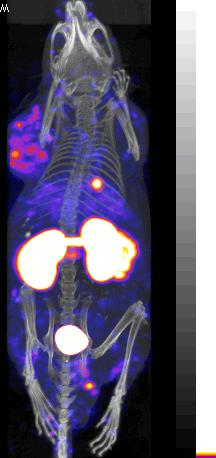

[64Cu] labeled Peptide tumor image